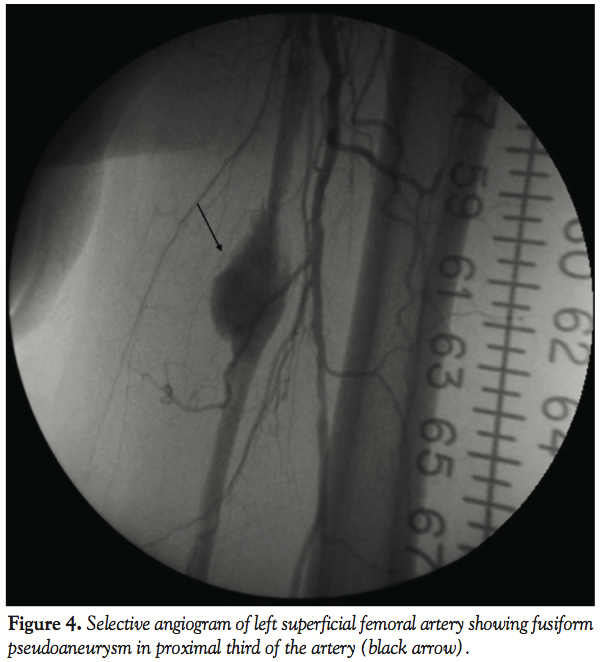

The patient was discharged home the following day without complications. A week later, the patient presented to the hospital with acute onset and worsening pain in his left thigh over the last 3 days and it was associated with ecchymosis and swelling. A CT angiography was performed and showed a fusiform aneurysm 4 cm x 27 mm diameter in the proximal third of the left SFA (Figure 3). Repeat angiogram confirmed the findings (Figure 4). Over a 0.014 ironman wire (Abbott Vascular), a 6.0 mm x 10 cm Viabahn endoprosthesis (W. L. Gore

& Associates) was deployed and postdilated by a 6.0 mm x 40 cm balloon at nominal pressure at 9 atm. There was a persistent leak at the distal part of the aneurysm, so another 7.0 mm x 5 cm Viabahn stent was placed and again postdilated by a 6.0 mm x 40 mm compliant balloon at nominal pressure. Final angiogram showed successful exclusion of the pseudoaneurysm (Figure 5) and the patient tolerated the procedure well with no complications. One week later, the patient again presented to the hospital for worsening pain in his left thigh. Repeat CT angiography showed patent stent grafts with resolution of pseudoaneurysm. The patient’s symptoms improved by using a lidocaine patch and ibuprofen with no new symptoms in the 6 months follow-up.